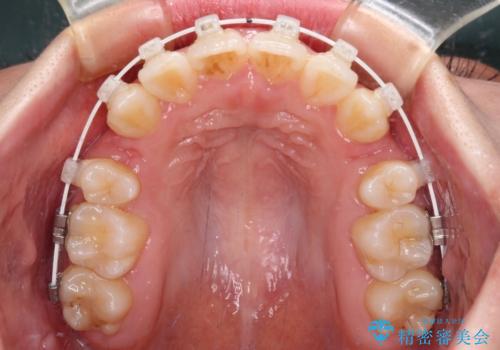

- 審美装置

- 上下前歯の八重歯やデコボコと、唇の閉じにくさを気にして来院された患者様です。

口元の突出感を改善するため、上下左右の第一小臼歯4本を抜歯し、ワイヤー装置にて矯正治療を行うこととしました。

デコボコの解消で歯が磨きやすくなり、抜歯矯正により口元の突出感が大幅に改善され、スッキリした口元になりました。